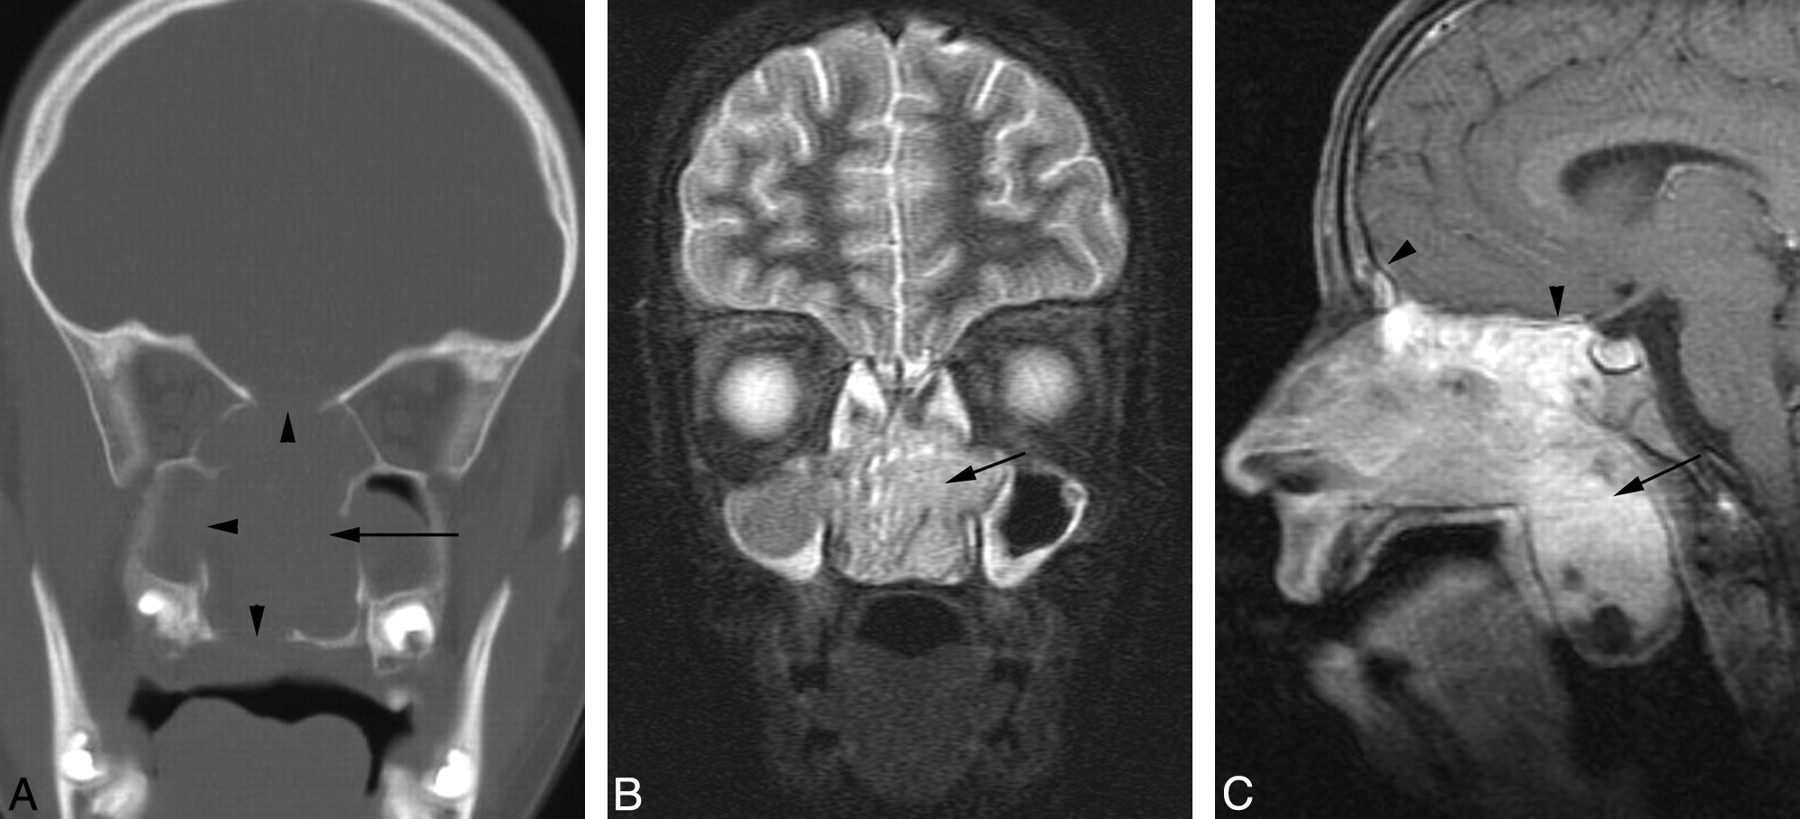

A 12-year-old girl presented with 3 weeks of upper respiratory tract symptoms, having been treated with 2 courses of antibiotics without improvement. Contrast-enhanced MR imaging revealed an 83-mm × 41-mm × 60-mm mass located in the midline within the nasal cavity (Fig 4). The mass obstructed the nasopharynx and protruded into the upper oral cavity. Superiorly and laterally, it extended into the contiguous paranasal sinuses. There was erosion of the planum sphenoidale and adjacent dural enhancement. The tumor had a relatively short T2 relaxation time but was hyperintense relative to muscle, with the pulse parameters used on the FSEIR images, and enhanced avidly apart from a few small cystic or necrotic components. CT scan obtained 11 days after the MR imaging examination demonstrated a moderately enhancing mass located in the midline within the nasal cavity, with lytic destruction of the contiguous paranasal sinuses and right orbit, extension into the right orbital apex, and erosion of the palate and pterygoid plates (Fig 4). There was erosion of the central skull base with tumor progression and intracranial spread of tumor into the epidural space overlying the planum sphenoidale. The maxillary antra and ethmoid air cells appeared opacified because of obstructed secretions. Biopsy results revealed poorly differentiated squamous carcinoma. Results of in situ hybridization for EBER were negative. FISH showed t(15;19). The pathologic features are described in further detail elsewhere.8

Patient 4. Sinonasal carcinoma t(15;19). A, CT scan demonstrates a midline sinonasal tumor (arrow) with lytic bony destruction of the paranasal sinuses and hard palate (arrowheads). B, Coronal FSEIR MR demonstrates the tumor (arrow), which had a relatively short T2 relaxation time but was hyperintense relative to muscle. C, Sagittal gadolinium-enhanced, fat-suppressed T1-weighted MR image demonstrates enhancing tumor (arrow) extending into the nasopharynx. There is dural enhancement superiorly (arrowheads).